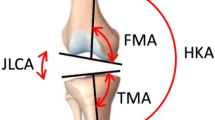

Three-dimensional landmarks were automatically calculated on each bone [18]. Landmarks sometimes falling between CT slices can be miscalculated in 2D analyses. Utilizing a 3D approach ensures all landmarks are anatomically accurate in three dimensions (Fig. 3). Using these landmarks, a set of linear and angular measurements was calculated on the distal femur (Fig. 4) and proximal tibia (Fig. 5). In total, 11 femoral (Table 1) and nine tibial (Table 2) measurements were recorded.

A diagram illustrates measurements on the distal femur. TEA = transepicondylar axis length; APH = anteroposterior height; MAP = medial anteroposterior height; LAP = lateral anteroposterior height; AP_AD = anteroposterior angle difference; AML = anterior mediolateral length; PML = posterior mediolateral length; DML = distal mediolateral length.

A diagram illustrates measurements on the proximal tibia. ML = mediolateral width; AP = anteroposterior height; EM_W = eminence width; TEVA = tuberosity eminence vector angle; LPW = lateral plateau mediolateral width; LPH = lateral plateau anteroposterior height; MPW = medial plateau mediolateral width; MPH = medial plateau anteroposterior height.

Using the above measurements, three normalized ratios that best describe femoral shape were calculated: mediolateral width/anteroposterior height (ML/AP), anterior mediolateral length/posterior mediolateral length (AML/PML), and medial anteroposterior height/lateral anteroposterior height (MAP/LAP). These ratios were used to classify and describe the shapes of femora: Type I and II with regard to ML/AP, Type III and IV based on AML/PML, and Type V and VI based on LAP/MAP (Fig. 6). Type I femurs are more square in shape with a ML/AP closer to 1 whereas Type II femurs have a higher ratio and are more rectangular in shape. Type III femurs are more triangular with a smaller AML/PML ratio whereas Type IV femurs are more rectangular. A smaller MAP/LAP ratio implies a lesser angle between the anterior and posterior condylar axes, indicating a Type V femur, whereas the anterior and posterior condylar axes are more parallel to one another in Type VI femurs. Three ratios were also calculated on the tibia: ML/AP, lateral plateau width/lateral plateau height (LPW/LPH), and medial plateau width/medial plateau height (MPW/MPH).

A diagram illustrates the six classifications used to describe femoral shape based on three normalized ratios. Type I and Type II classify femoral shape relative to mediolateral width/anteroposterior height (ML/AP), Type III and Type IV classify femoral shape relative to anterior mediolateral length/posterior mediolateral length (AML/PML), and Type V and Type VI classify femoral shape relative to medial anteroposterior height/lateral anteroposterior height (MAP/LAP).